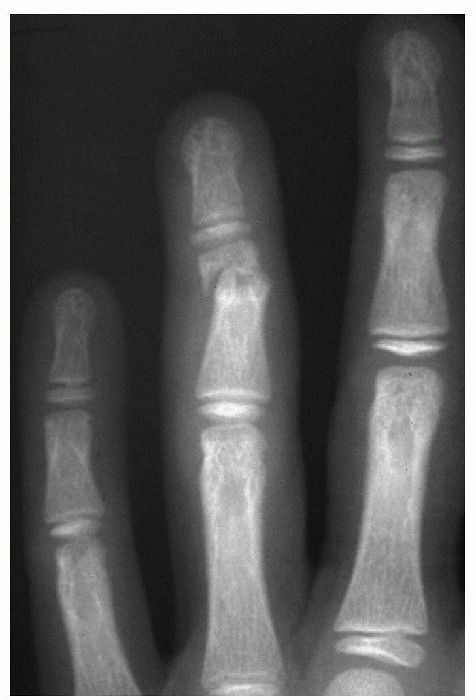

for all physeal fractures after phalanx and wrist. The physis fracture

![]() |

Figure 12.3-4 Classification of lateral condyle fractures. (A) Milch type I, lateral view (Salter-Harris type IV). (B) Milch type II, lateral view (Salter-Harris type II).

Account for 20% of distal humerus fractures.

The commonest fracture line travels from

trochlea (Milch type II) (Fig.12.3-4). -

The rare fracture line type starts from